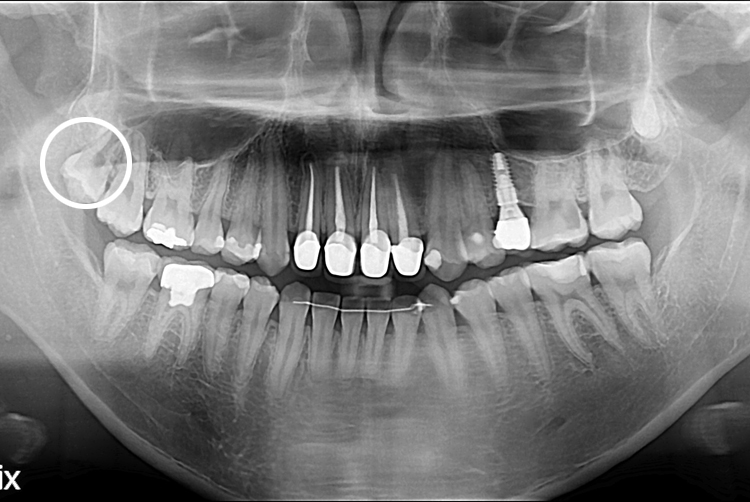

[사랑니] 단순매복 사랑니 발치

치료후 : 2021-03-09

세종치과는 구강악안면외과학 박사이신 원장님이 발치하는 치과 입니다.